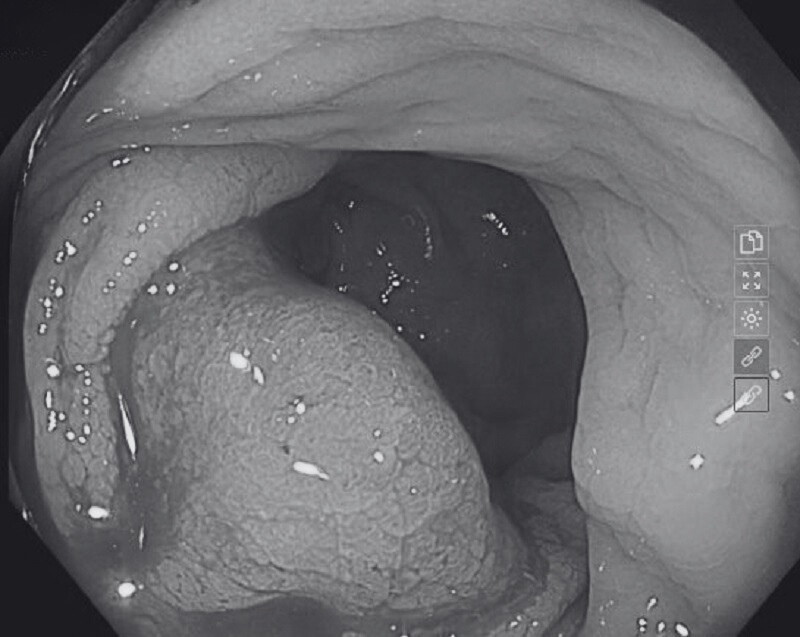

Nội soi đại trực tràng phát hiện khối u chiếm khoảng 2/3 chu vi lòng đại tràng kích thước xấp xỉ 4cm

Nội soi đại trực tràng ống mềm, tại đại tràng ngang - xuống, niêm mạc rải rác có vài polyp kích thước 0.3-0.8cm. Vị trí trực tràng: cách hậu môn khoảng 10cm có khối u chiếm khoảng 2/3 chu vi lòng đại tràng kích thước xấp xỉ 4cm, bề mặt cứng chắc, chạm vào dễ chảy máu. Trước dấu hiệu nghi ngờ này, ngay trong khi nội soi, các bác sĩ đã tiến hành sinh thiết làm mô bệnh học. Kết luận: Polyp đại tràng, K trực tràng, trĩ nội độ I.